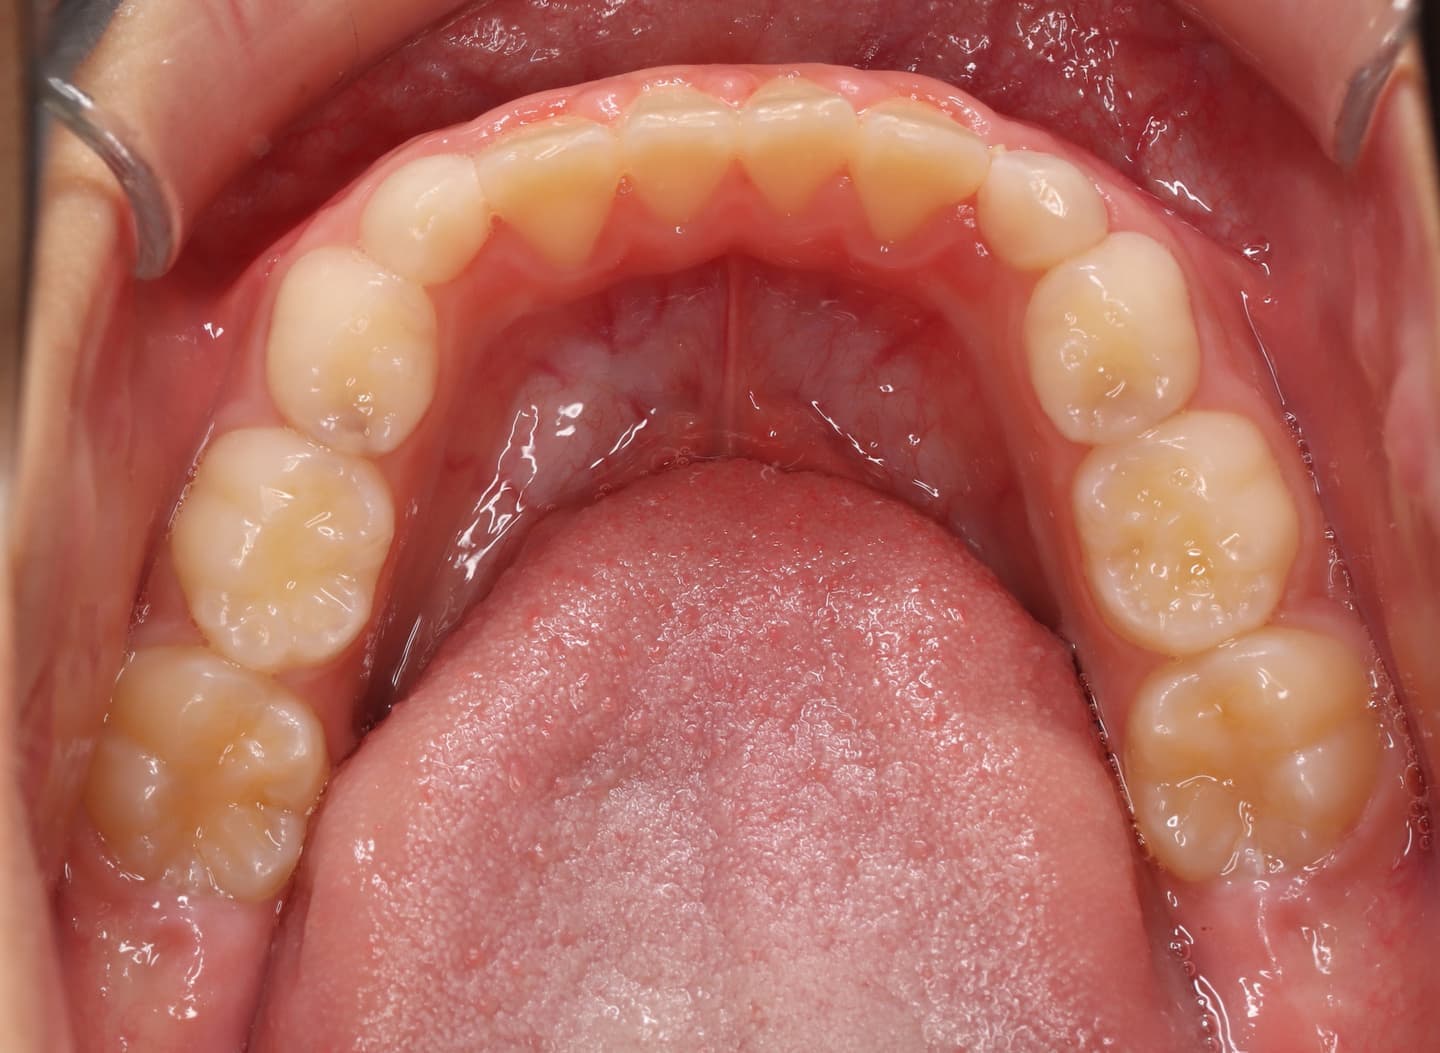

治療前

右上乳犬歯が既に脱落しており、右上犬歯の萌出スペースがゼロになっています。